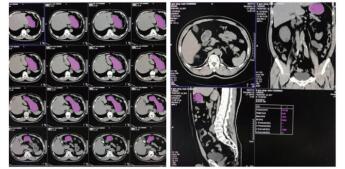

1.3 CT计算胃残余量和超声测定胃窦截面积⑴CT计算胃残余量:使用64排128层4D螺旋CT机(SOMATOM Definition AS型,德国SIEMENS公司)进行腹部CT检查,然后利用VOLUME-Work Flow医学图像软件(德国SIEMENS公司)对CT图像进行分析,即以Freehand方式对胃进行描记,从胃底开始逐层勾画胃壁轮廓形态并进行修正,以及设置CT评估限值,最终通过软件自动计算出胃腔总容积、胃腔气体容积、胃腔非气体容积及胃腔容积高度,其中胃腔非气体容积为患者胃残余量值(见图 1)。

| 图 1 CT检测胃容积的方法(左:描计胃轮廓;右:胃残余量计算) Fig 1 The capacity of stomach measured by CT (Left, the tracing of gastric outline; Right, the calculation of gastric residual volume) |